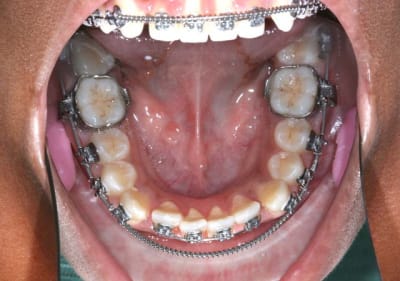

2°) Appareillage MB. Sup et 2 mois après Inf., avec mes Bk. modifiés en position Damon

On peut observer un décalage des points inter-incisifs et des rotations des Inc. Inf.

Voir Photo

@ suivre Bjc.